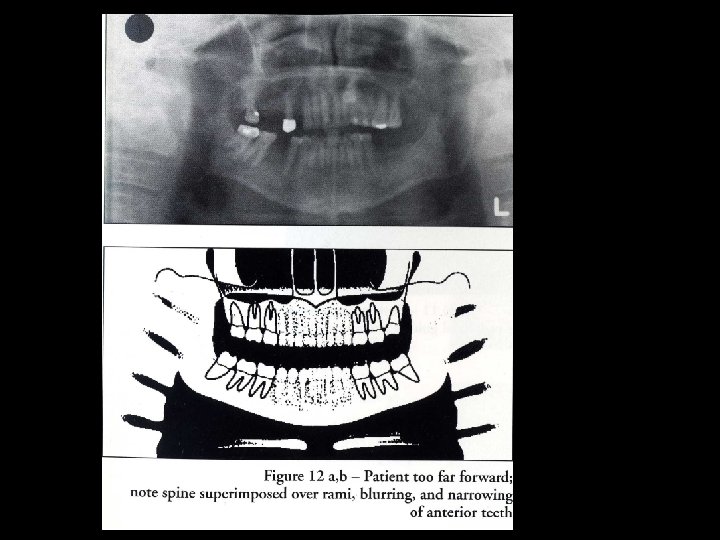

Ghost image